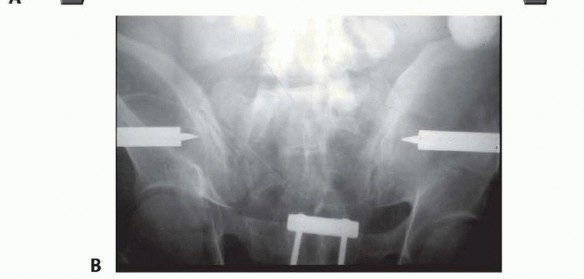

### FIG 5 • The anterior hemipelvis offers two sites for pin insertion: the iliac crest (superiorly) and the supraacetabular region (more inferiorly). A. Profile view. B. Frontal view. Pin placement within the iliac crest is more expeditiously performed and lacks significant regional anatomic hazards. On occasion, this area may be compromised by soft tissue concerns or proximity to fracture planes. In such cases, pin placement within the supra-acetabular region is an option. Pins and frames in this lower position may offer improved access to the abdomen and, unlike pins placed within the iliac crest, are less irritating to anterolateral abdominal soft tissues. 19 In an obese patient, these pins (supra-acetabular) may be better tolerated and less prone to loosening and infection. The dense bone of the supra-acetabular region offers stability of fixation as good as or better than the iliac crest. Some authors investigating the biomechanical performance of these pins (supra-acetabular) demonstrated superior purchase within bone and diminished displacement of posterior portions of the pelvic ring. 12 Because supra-acetabular pin insertion is more time consuming and instrumentation and fluoroscopy dependent, its role as a resuscitative measure is limited. The pelvic antishock clamp (C-clamp) is a posteriorly (or trochanteric) applied device that may offer greater stability to vertically unstable fractures than anteriorly applied frames ( FIG 6).1, 11 It is designed for the emergent treatment of unstable pelvic ring injuries. The device is indicated in both rotationally and vertically unstable pelvic ring injuries. It is contraindicated in lateral compression injuries and fractures involving comminution of the iliac wing or sacrum. If the device is used in lateral compression-type injuries, it may accentuate the deformity. Use of the pelvic 314 antishock clamp with iliac wing fractures may lead to the pins traversing the fracture sites, subsequently causing internal injury.

---

### FIG 6 • “Antishock” clam This device, applied posteriorly, may offer more stability to vertically unstable injury patterns than anteriorly applied frames. A. Schematic. B. Case AP radiograph. (A: Modified from Simonian PT, Routt ML Jr, Harrington RM, et al. Anterior versus posterior provisional fixation in the unstable pelvis: a biomechanical comparison. Clin Orthop Relat Res 1995;310:245-251.) Despite advances in contemporary pelvic external fixation, concerns and complications associated with its application remain. Among these include poor patient tolerance, loss of reduction as well as pin tract sepsis, and loosening. In an effort to obviate these, the introduction of a subcutaneous internal anterior fixator has been described. 29 This technique employs either a precontoured rod or plate, which is introduced via small incisions at the level of the anterior inferior iliac spine (AIIS). A subcutaneous tunnel overlying the external oblique fascia is established through which the device is delivered and anchored within the dense bone of the supraacetabular region bilaterally. Close proximity to underlying intrapelvic and neurovascular structures demands an understanding of regional anatomy and proper surgical technique. 16, 30 It is not applicable for resuscitative purposes, as its fluoroscopic and insertion times can be intensive. Attributes include enhanced patient mobilization and low documented rates of infection. Its most unique indication may be in obese individuals. 31 Obligatory removal in an operating room setting remains a relative disadvantage. ## TECHNIQUES